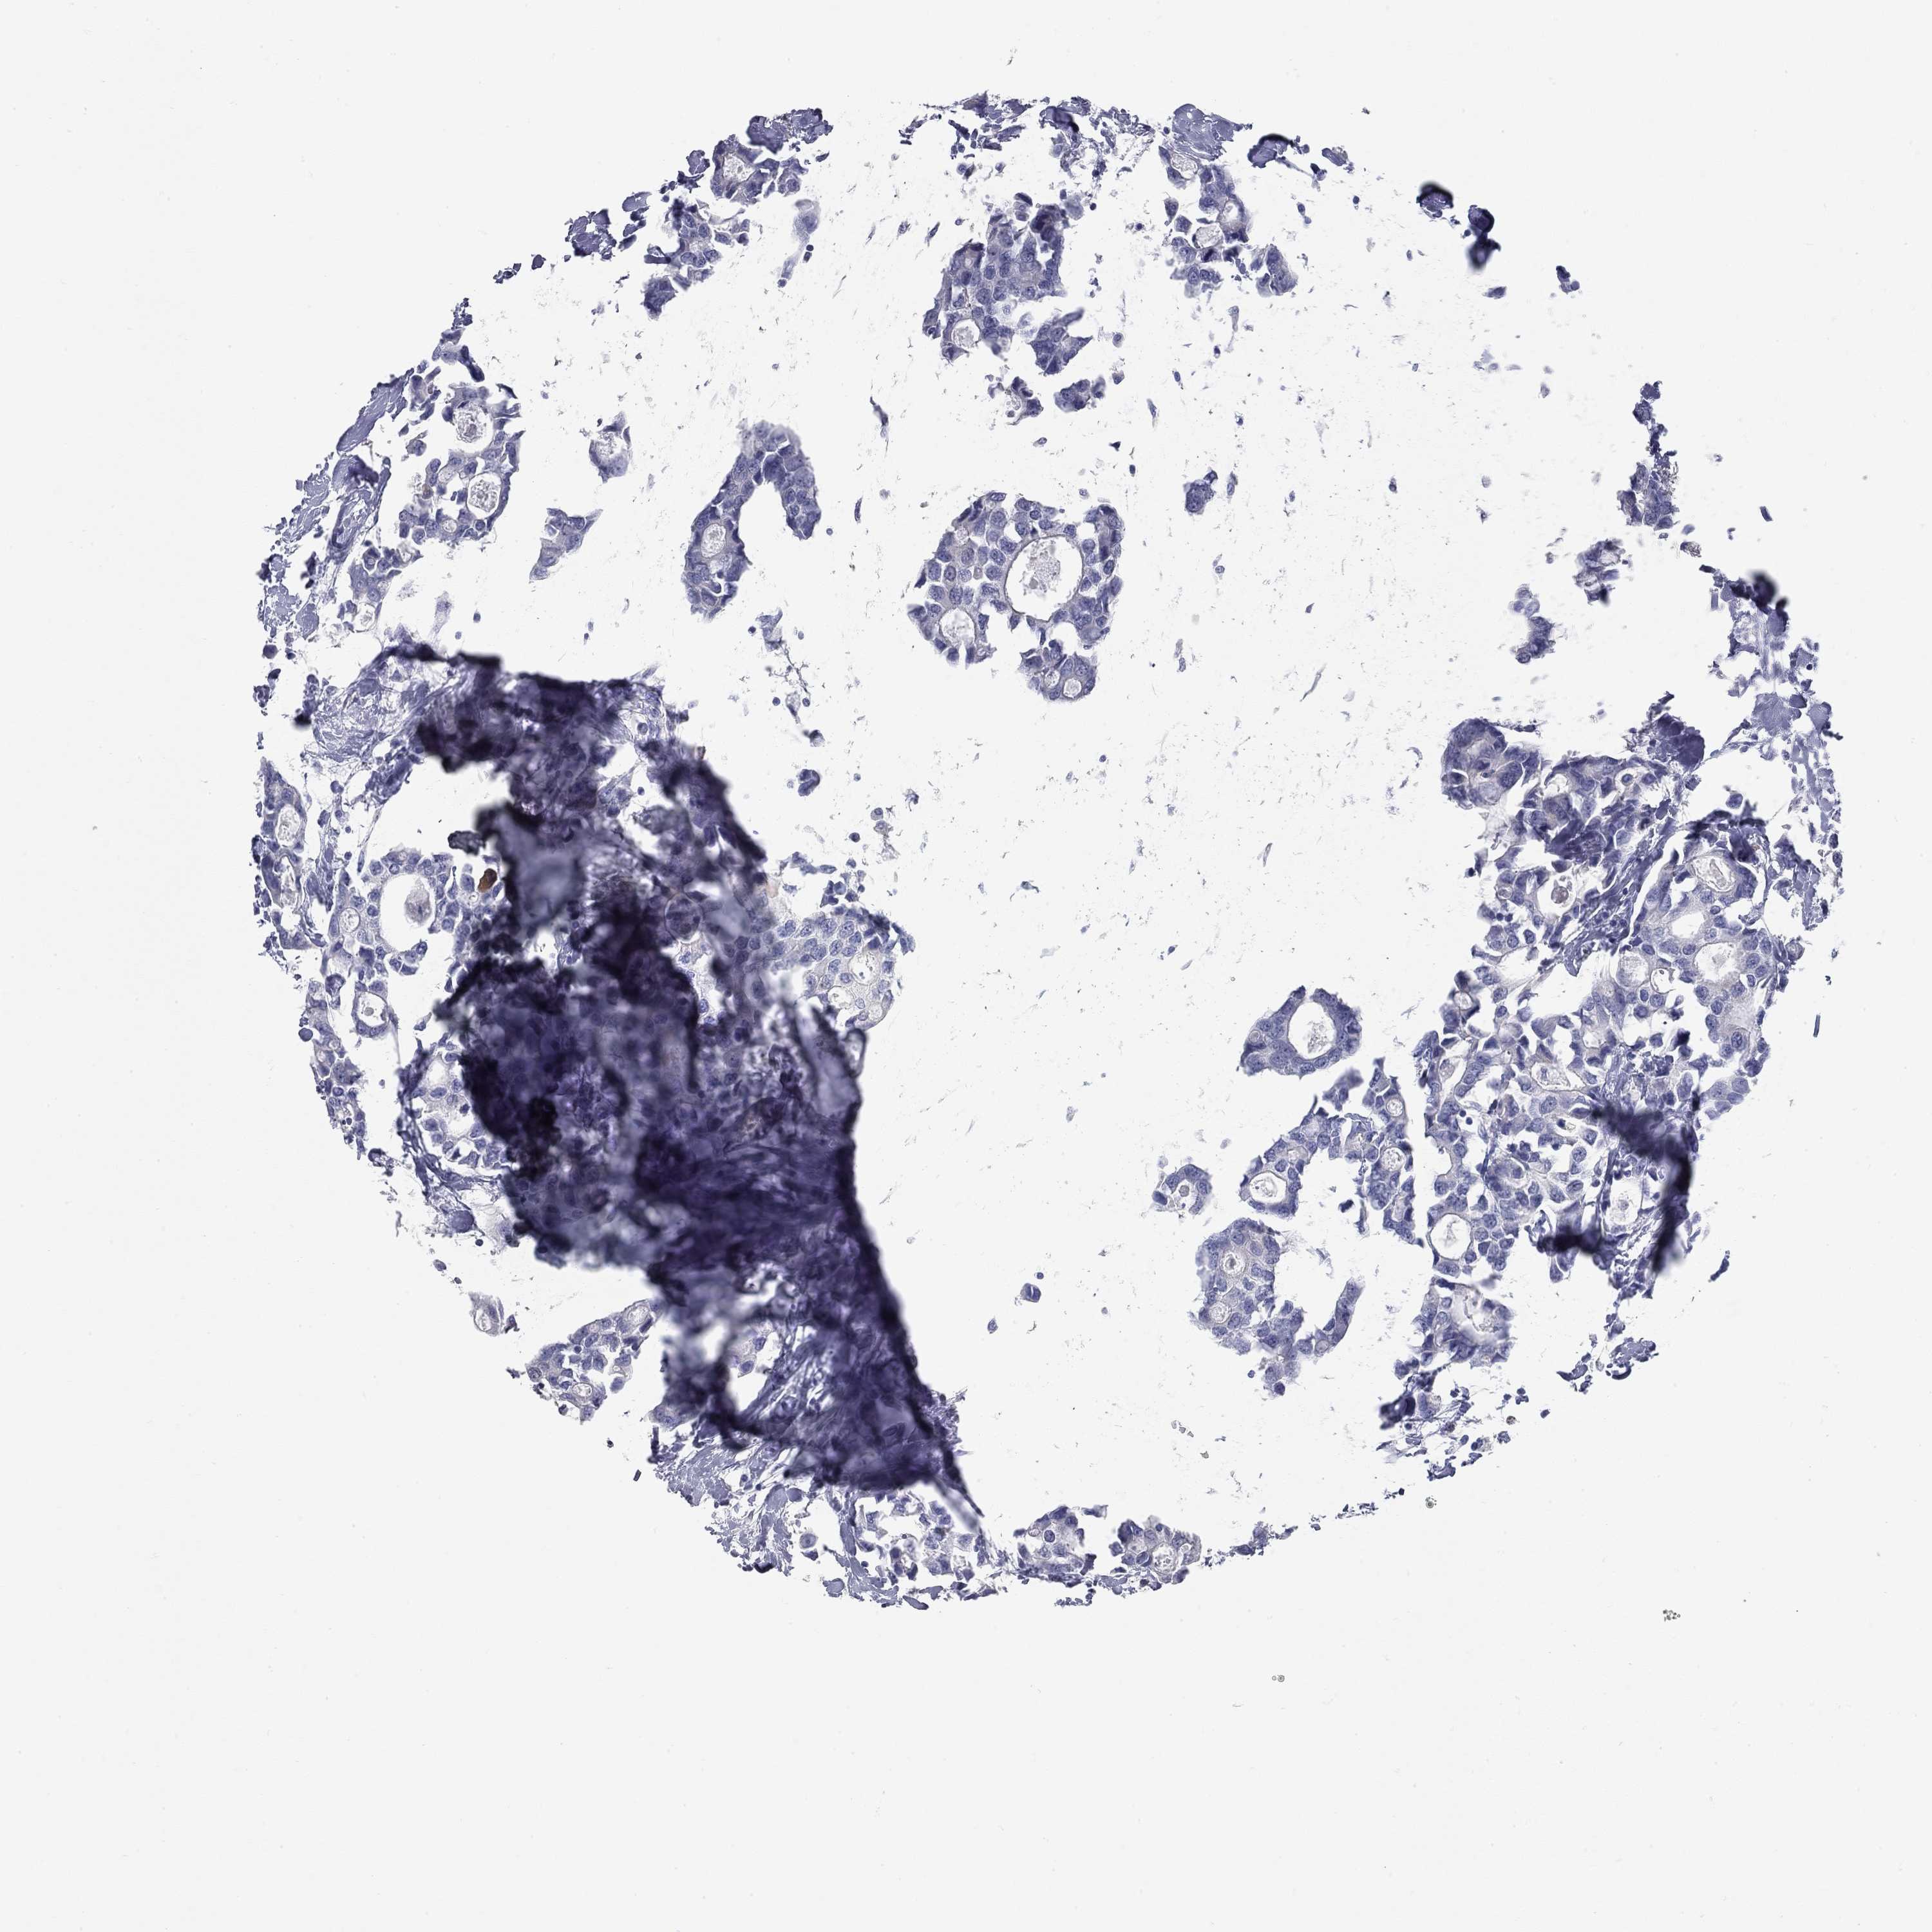

CANCER BREAST CANCER Show tissue menu

BRCA TCGA BRCA VALIDATION PROTEIN EXPRESSION

ANTIBODIES

AND

VALIDATION